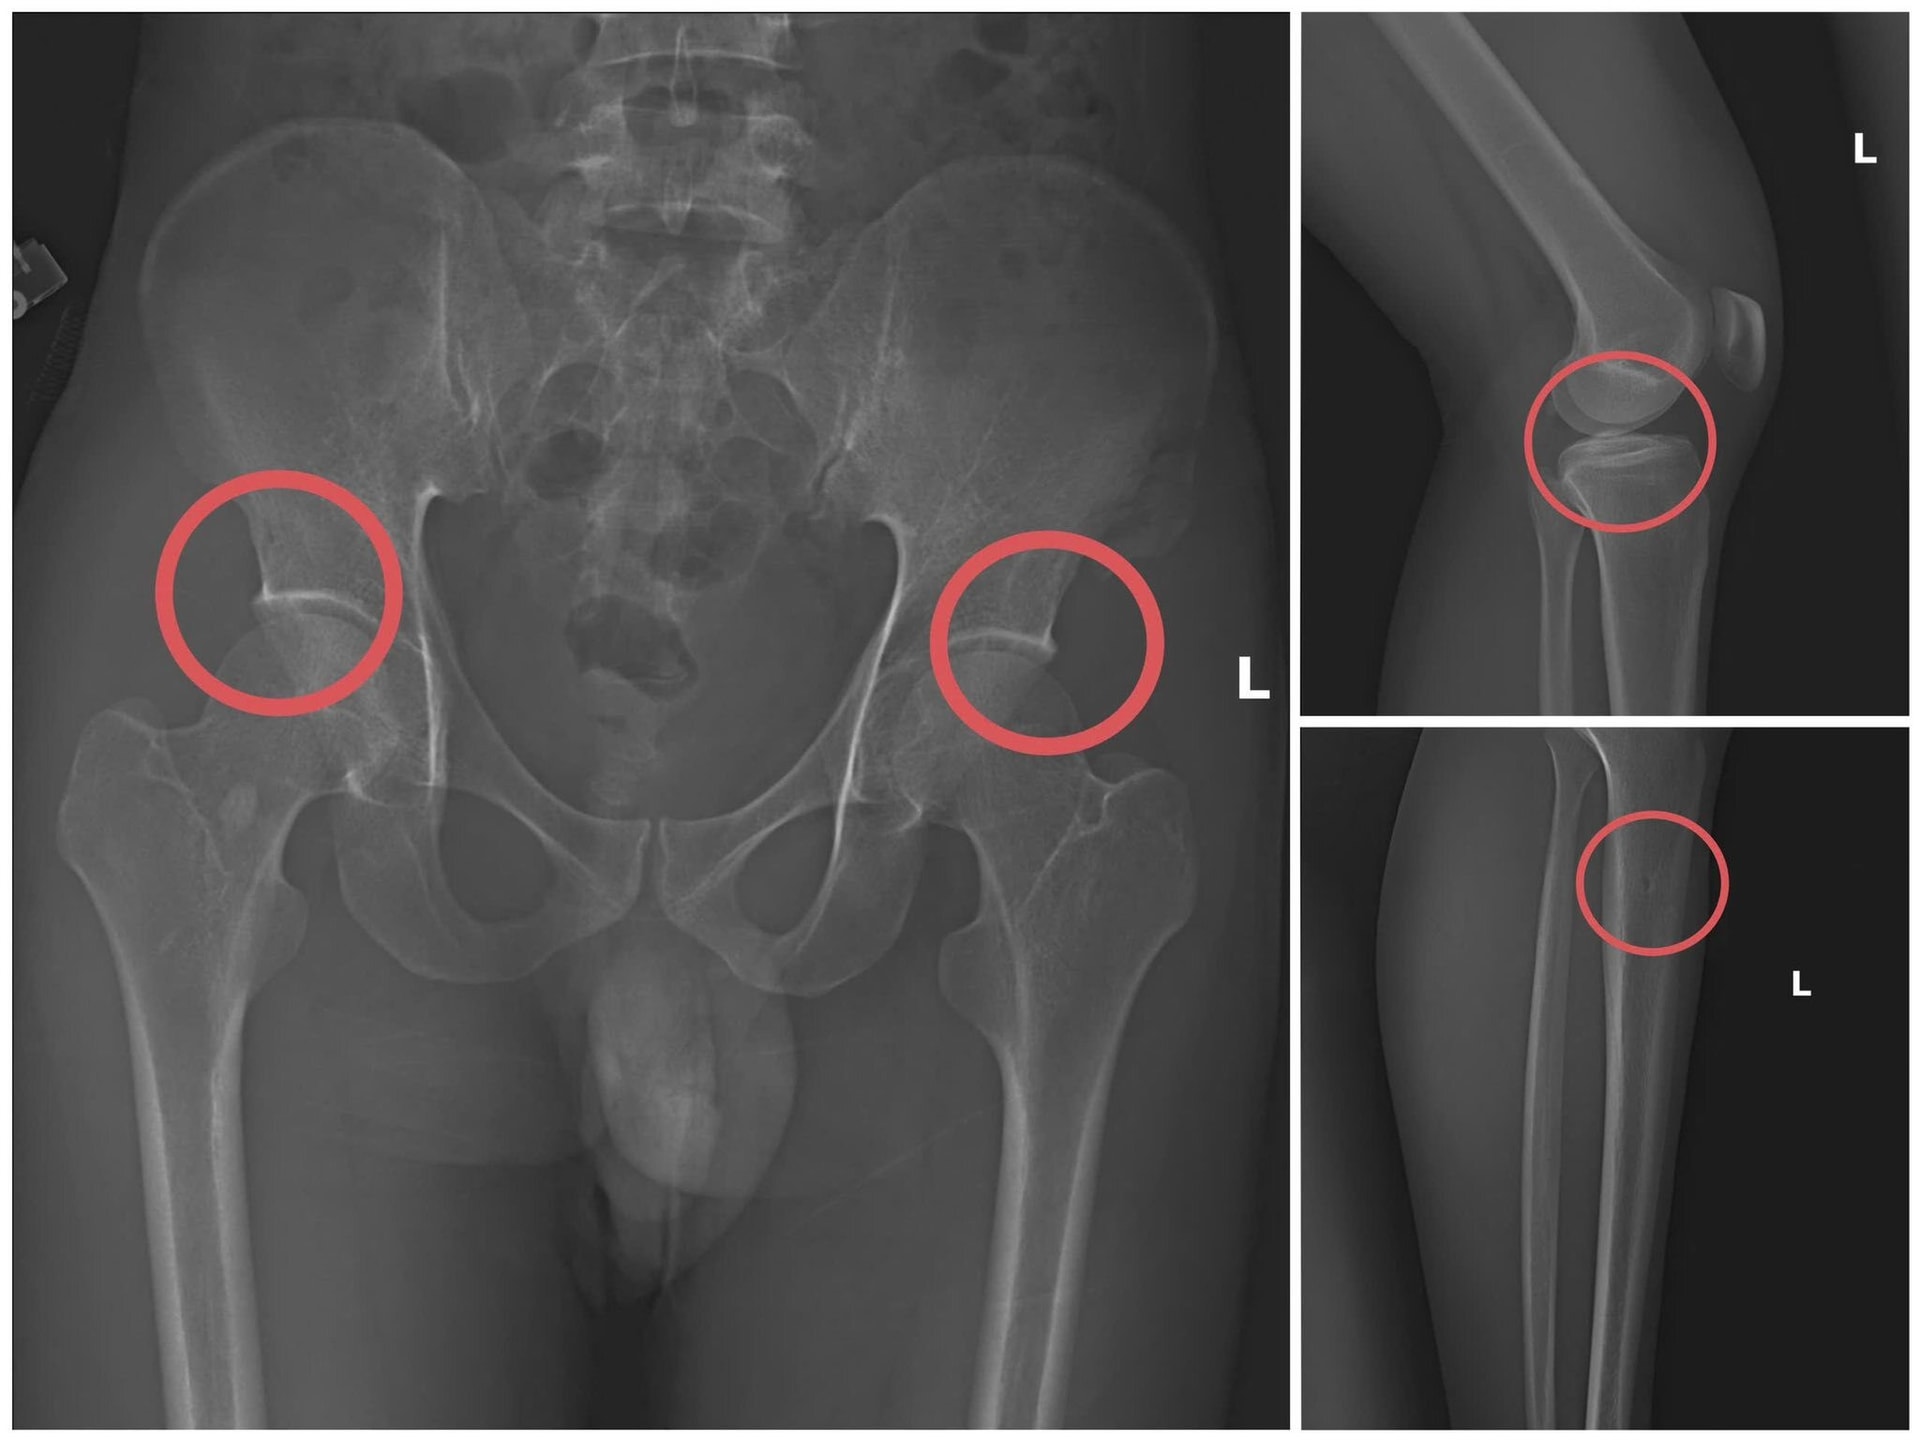

Lợi dụng thời gian dài công tác trong ngành và am hiểu cấu trúc xương, khớp, Châu đã xây dựng quy trình trục lợi theo chuỗi khép kín gồm: Vận động người mua bảo hiểm nhân thọ, trực tiếp gây thương tích bằng thuốc mê và các dụng cụ tác động lực, sau đó dựng hiện trường giả để hợp thức hóa hồ sơ điều trị.

Đáng chú ý, Châu trực tiếp thực hiện hành vi tiêm thuốc mê rồi dùng kim tiêm, búa để tác động vào xương người mua bảo hiểm, tạo nên các vết vỡ xương tương tự tai nạn thật. Khi thương tích đã tạo xong, Châu tiếp tục hướng dẫn các đối tượng dựng hiện trường giả như điện giật ngã, trượt chân ngã suối nhằm hợp thức hóa bệnh án và hoàn thiện hồ sơ yêu cầu chi trả.